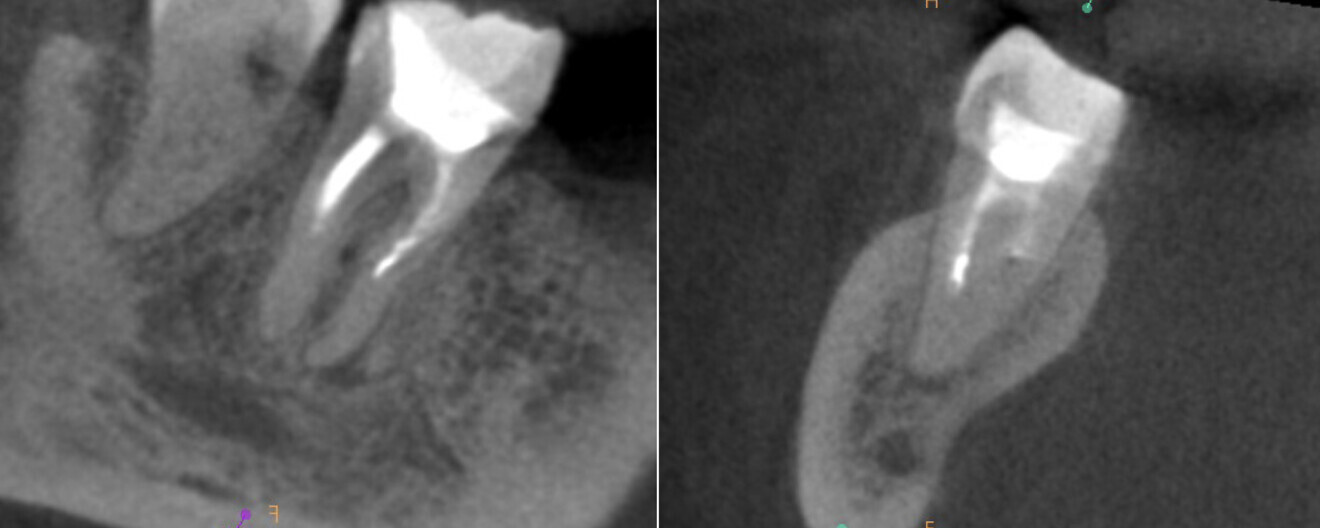

To confirm that the mesial root had been filled properly, the patient was referred for a CBCT scan. The examination revealed that the MB2 canal had been filled with the sealing material and that there was an isthmus between the MB1 and MB2 canals in the apical third of the root and two separate portals of exit (Fig. 14). The tooth was restored with composite resin, and the patient was referred for an indirect restoration with cusp coverage and scheduled for a recall appointment in six months.

At the recall appointment, the CBCT examination found no signs of inflammation. The tooth was asymptomatic, and the Schneiderian membrane was not enlarged (Fig. 15).

Fig. 14

Figs. 15a & b